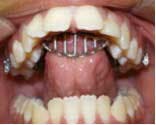

Prolonged thumb-sucking can cause a dental and even a skeletal open bite

Prolonged thumb-sucking turns into a habit that can cause a dental and even a skeletal open bite. If the habit ceases while the child is still growing, the dental open bite can self-correct, but sometimes the help of a dentist or an orthodontist is required to correct the position of the teeth and align the jaws. Oftentimes the actual thumb-sucking may stop, but the child develops a tongue-thrusting habit while eating, speaking, and swallowing. This tongue-thrusting then perpetuates the deleterious force on the dentition and jaws. If the open bite is not corrected while the child is growing, then jaw surgery may be required to correct the bite.